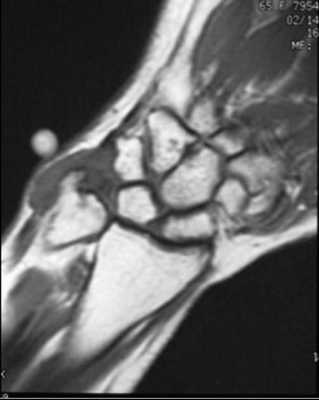

МРТ кисти. Корональная Т1-взвешенная МРТ. Нормальное изображение ладьевидно-полулунной связки. Обозначения: S - ладьевидная кость (scaphoid), L - полулунная кость (lunatum), T- трехгранная кость (triquetrum).

МРТ кисти. Корональная градиентная МРТ. Нормальное изображение полулунно-трехгранной связки. Обозначения: S - ладьевидная кость (scaphoid), L - полулунная кость (lunatum), T- трехгранная кость (triquetrum).